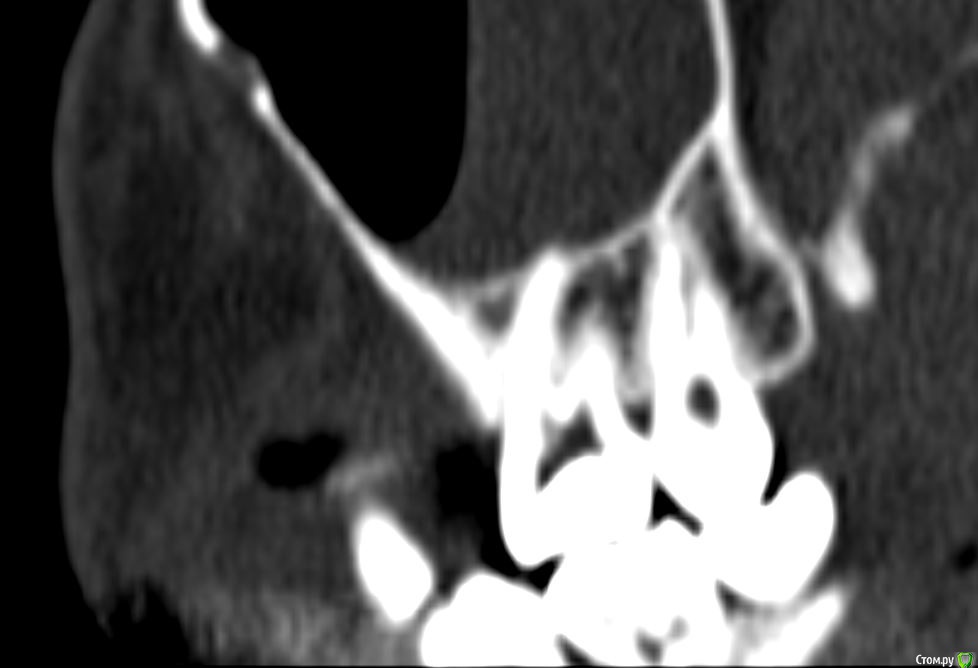

Лисица Опубликовано 26 июля, 2015 Автор Поделиться Опубликовано 26 июля, 2015 (изменено) Вы же не думаете, что Вам назначат а/б терапию по интернету? Я просто не знаю, исходя из каких показателей она назначается. Поэтому осведомилась на всякий случай. Итак, сходила я сегодня на КТ. И по ходу мне сделали что-то не то... Когда я обратилась в клинику, я уточнила, что мне нужно КТ для эндодонтии, чтобы видно было каналы, с достаточным разрешением, чтобы было видно зубы и их корни, входящие в верхнечелюстной синус. Администратор клиники уточнила у врача и сказала, что мне нужно заказывать не КТ верхней челюсти, а КТ пазух. У рентгенолога я также повторила все описанное, рассказала, что при лечении каналов вчера была продырявлена пазуха, уточнила, будут ли видны как следует зубы и их каналы, меня заверили, что "все будет". Причем у врача, судя по описанию на сайте клиники, была ординатура по хирургии в медико-стоматологическом университете, так что он, уж наверное, понимал, что мне нужно. В итоге я получила пленку со снимками формата чуть ли не А3 и диск. На пленке все зубы были просто белыми и коронки видны не целиком. Заключение: в правой верхнечелюстной пазухе уровень жидкости, острый правосторонний гайморит.Думала, может в программе можно будет увеличить разрешение. Но похоже, что нет... или я просто ламер? Зубы просто размытые и белые... Прилагаю сделанные мной скриншоты, как мне кажется, наиболее показательные... Если нужно другие "виды", то скажите какие, или такие снимки вообще ни о чем? Программа просмотра называется Philips DICOM Viewer R3.0-SP03. Аппарат был не местный "на голову", а здоровый, куда заезжаешь в лежачем положении. Изменено 26 июля, 2015 пользователем Лисица Ссылка на комментарий

St. Опубликовано 27 июля, 2015 Поделиться Опубликовано 27 июля, 2015 Гайморит справа есть, и жидкость тоже. Корни этого зуба действительно заканчиваются в гайморовой.Ничего такого страшного, чтоб однозначно удалять зуб я не вижу. С гайморитом - к лорам на лечение.В зубе я бы ещё раз поменяла лекарство на пару недель, пока гайморит не притихнет, потом постоянно пломбировать. 1 Ссылка на комментарий

Лисица Опубликовано 27 июля, 2015 Автор Поделиться Опубликовано 27 июля, 2015 St., большое спасибо за ответ! Моя врач планировала закрыть его в среду (зная о том, что пазуха проткнута). Если запломбировать, пока воспаление есть, какие могут быть проблемы? И еще она сказала, что нащупала 4-й тонкий канал, но не было времени его прочистить, так что она оставила как есть до среды. Сказала, что почистит и сразу же закроет. Судя по КТ, корня 3, значит в одном из них 2 канала? В 3D похоже, что корни с медиальной стороны сросшиеся какие-то... и на небном тоже борозда. Ссылка на комментарий